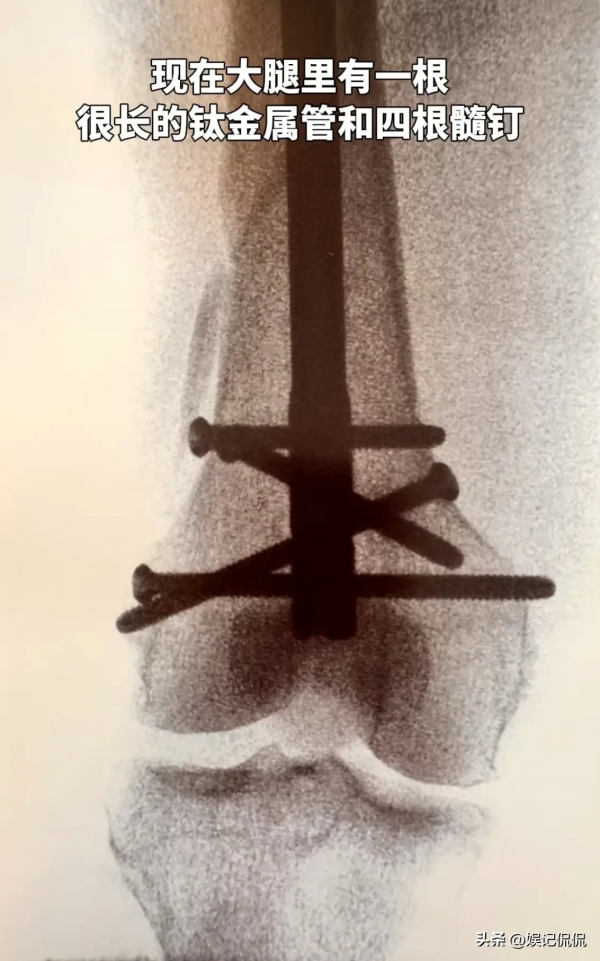

目前,向太已经通过微创手术完成了治疗,只是因为大腿骨断裂严重,因此只能植入一根钛金属管和4根髓钉固定。